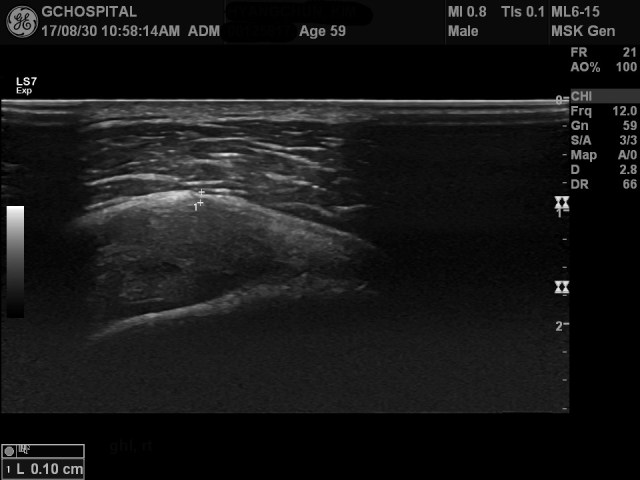

위 영상은, 같은 환자에서 증상이 없었던 오른쪽 어깨의 같은 부위에서 얻은 영상입니다.

coracohumeral ligament와 joint capsule이 서로 구분되지 않아서 둘의 두께를 함께 측정했는데도 1mm로 측정됩니다.

이처럼, 전형적인 adhesive capsulitis에서는 coracohumeral ligament뿐 아니라 joint capsule의 두께도 함께 두꺼워진다는 점, 그리고, 증상이 없는 다른쪽 어께와의 비교가 adhesive capsulitis의 진단에 매우 유용하다는 걸 확인할 수 있었던 사례입니다.